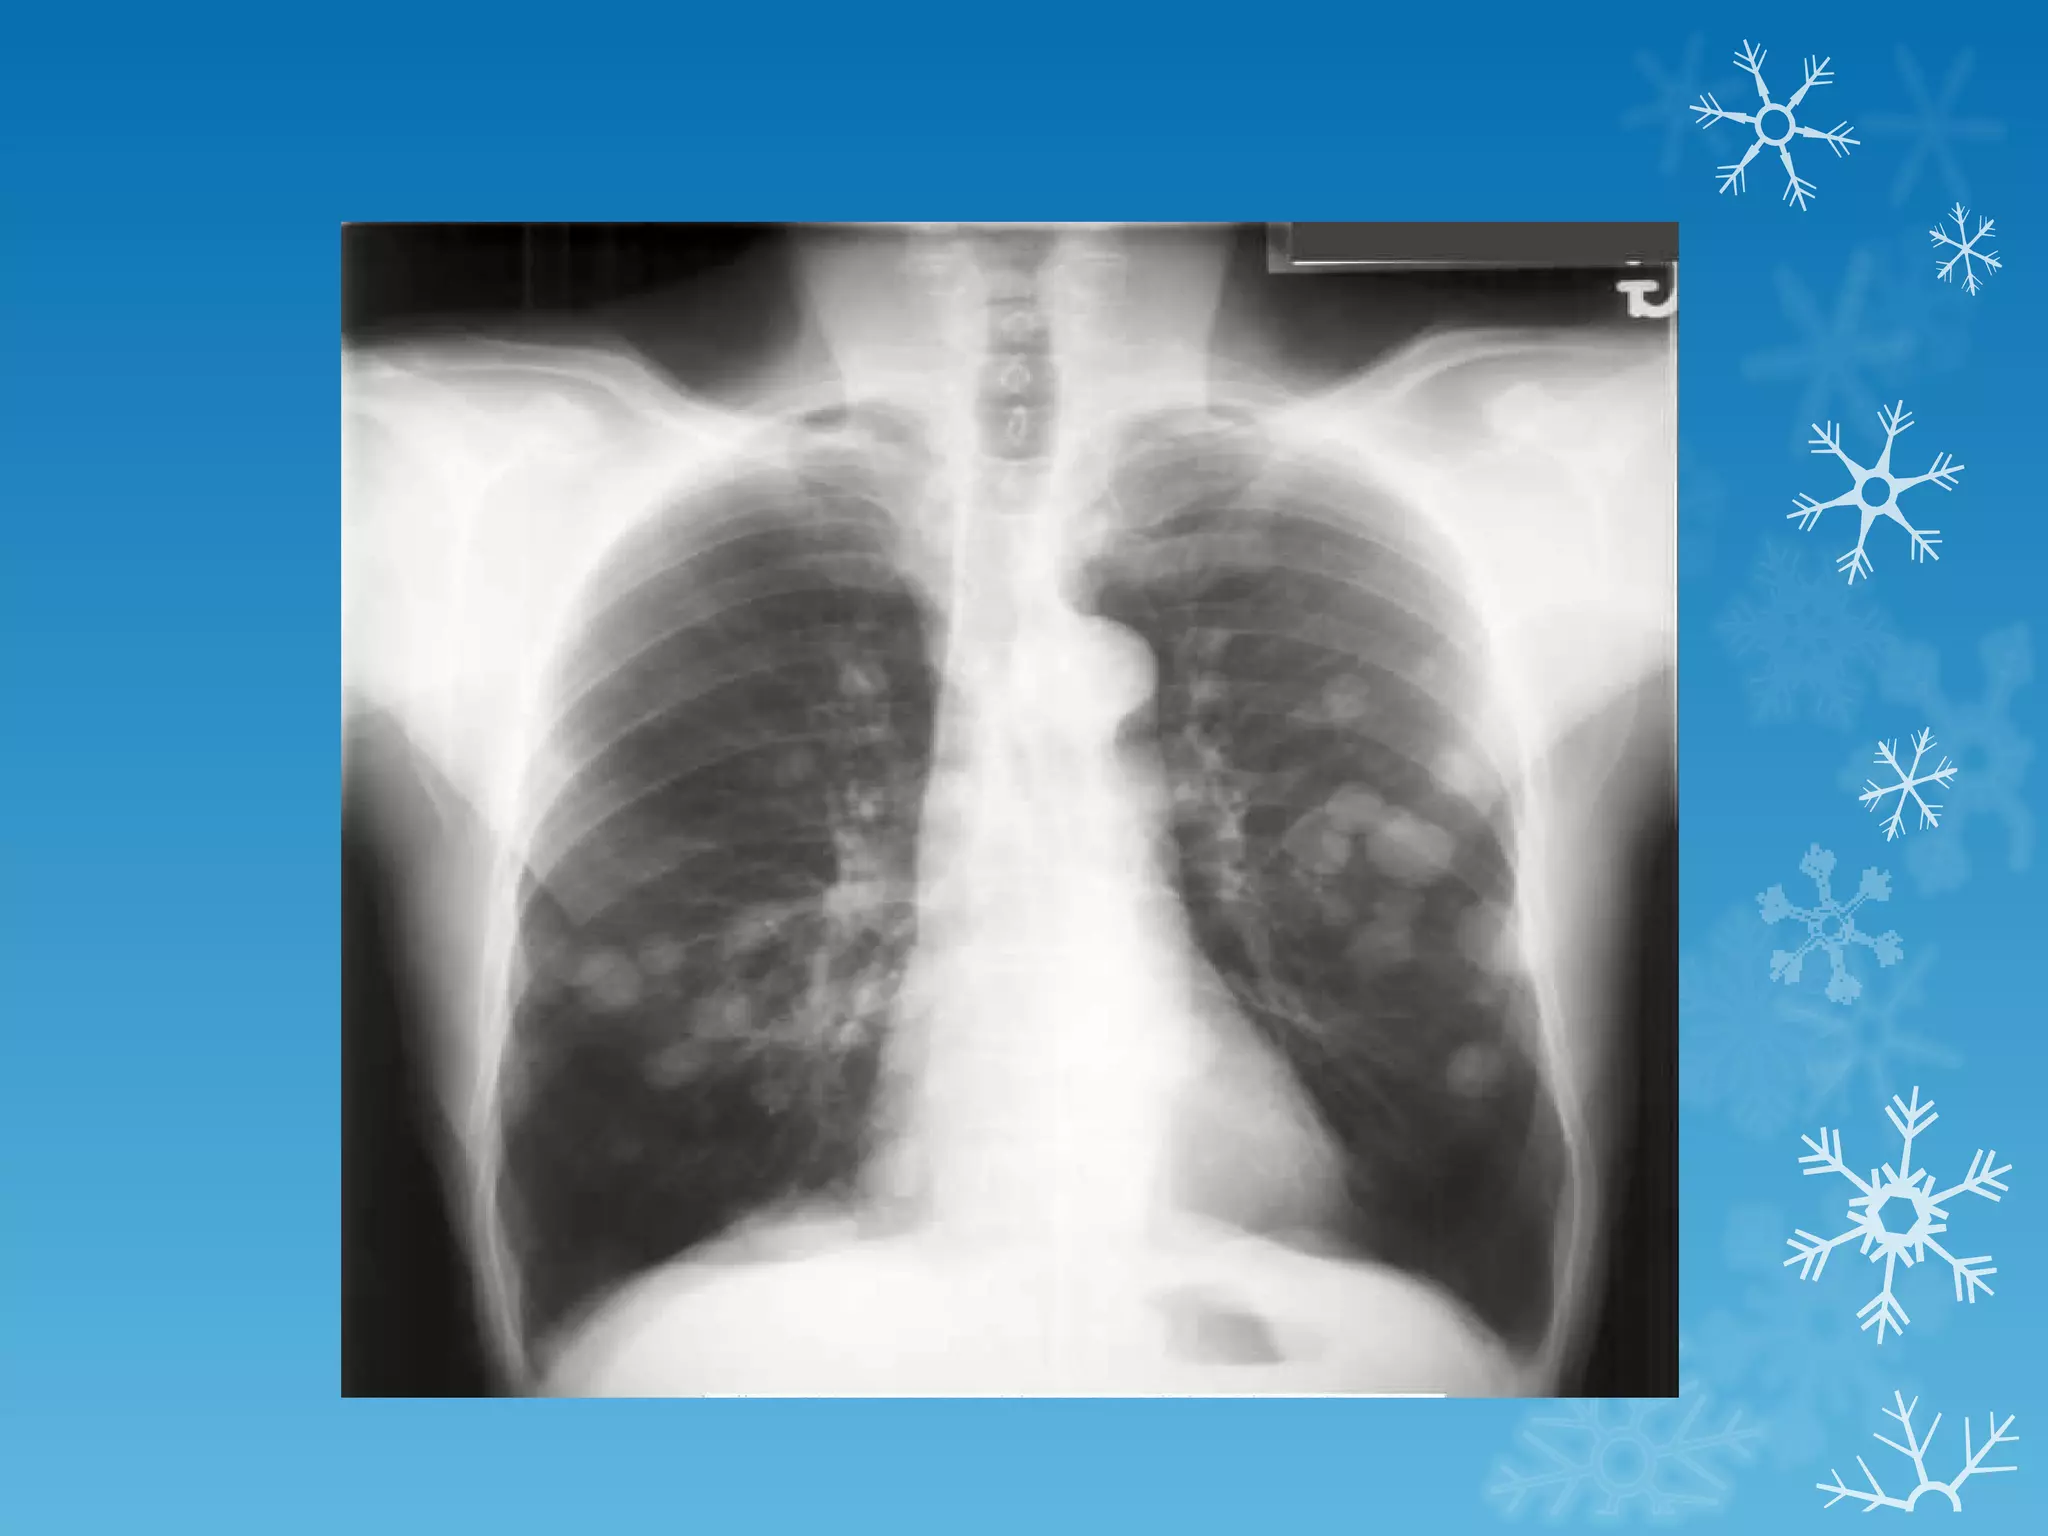

This document discusses chest x-ray interpretation and provides guidance on evaluating x-rays. It explains that tissue density determines how an x-ray beam penetrates, with denser tissues appearing whiter and less dense tissues appearing blacker. It also outlines different chest x-ray views and factors to consider like patient orientation, age, gender, and rotation. Abnormalities are described as appearing too white, too black, too large, or in the wrong place. The document stresses a systematic approach of identifying, localizing, describing lesions, and providing differential diagnoses.